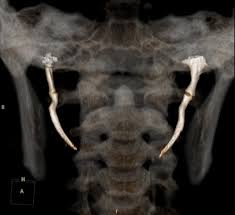

A Sindrome de Eagle é um diagnóstico difícil , mas que nós cirurgiões de Cabeça e Pescoço nos deparamos algumas vezes. Há 1 semana atrás no Ambulatório de Franca e hoje aqui no HC- Ribeirão Preto, em especial, atendi 1 caso muito parecido, com sintomatologias semelhantes. Uma dor inexplicável ao deglutir, uma dor no ouvido que não tem relação com infecção ou tumores, dor ao mobilizar a cabeça para o lado afetado e uma dor importante ao palpar a amigdala do mesmo lado. A causa geralmente se relaciona a um alongamento do processo estilóide e o exame que melhor mostra essa alteração é a Tomografia Computadorizada. Então fica a dica se vc está tendo algum sintoma para deglutir, uma dor inexplicável na faringe ou ouvido e já foram feitos exames para investigar outras causas e não se chegou a um diagnóstico. Procure uma avaliação para que seja feito um diagnóstico mais preciso. Lembrando que nem semopre um alongamento do processo estilóide em si é suficiente para causar a Sd de Eagle.

Mais informações: Management of Eagle Syndrome. Current Opinion in Otolaryngology & Head and neck Surgery, 2023.